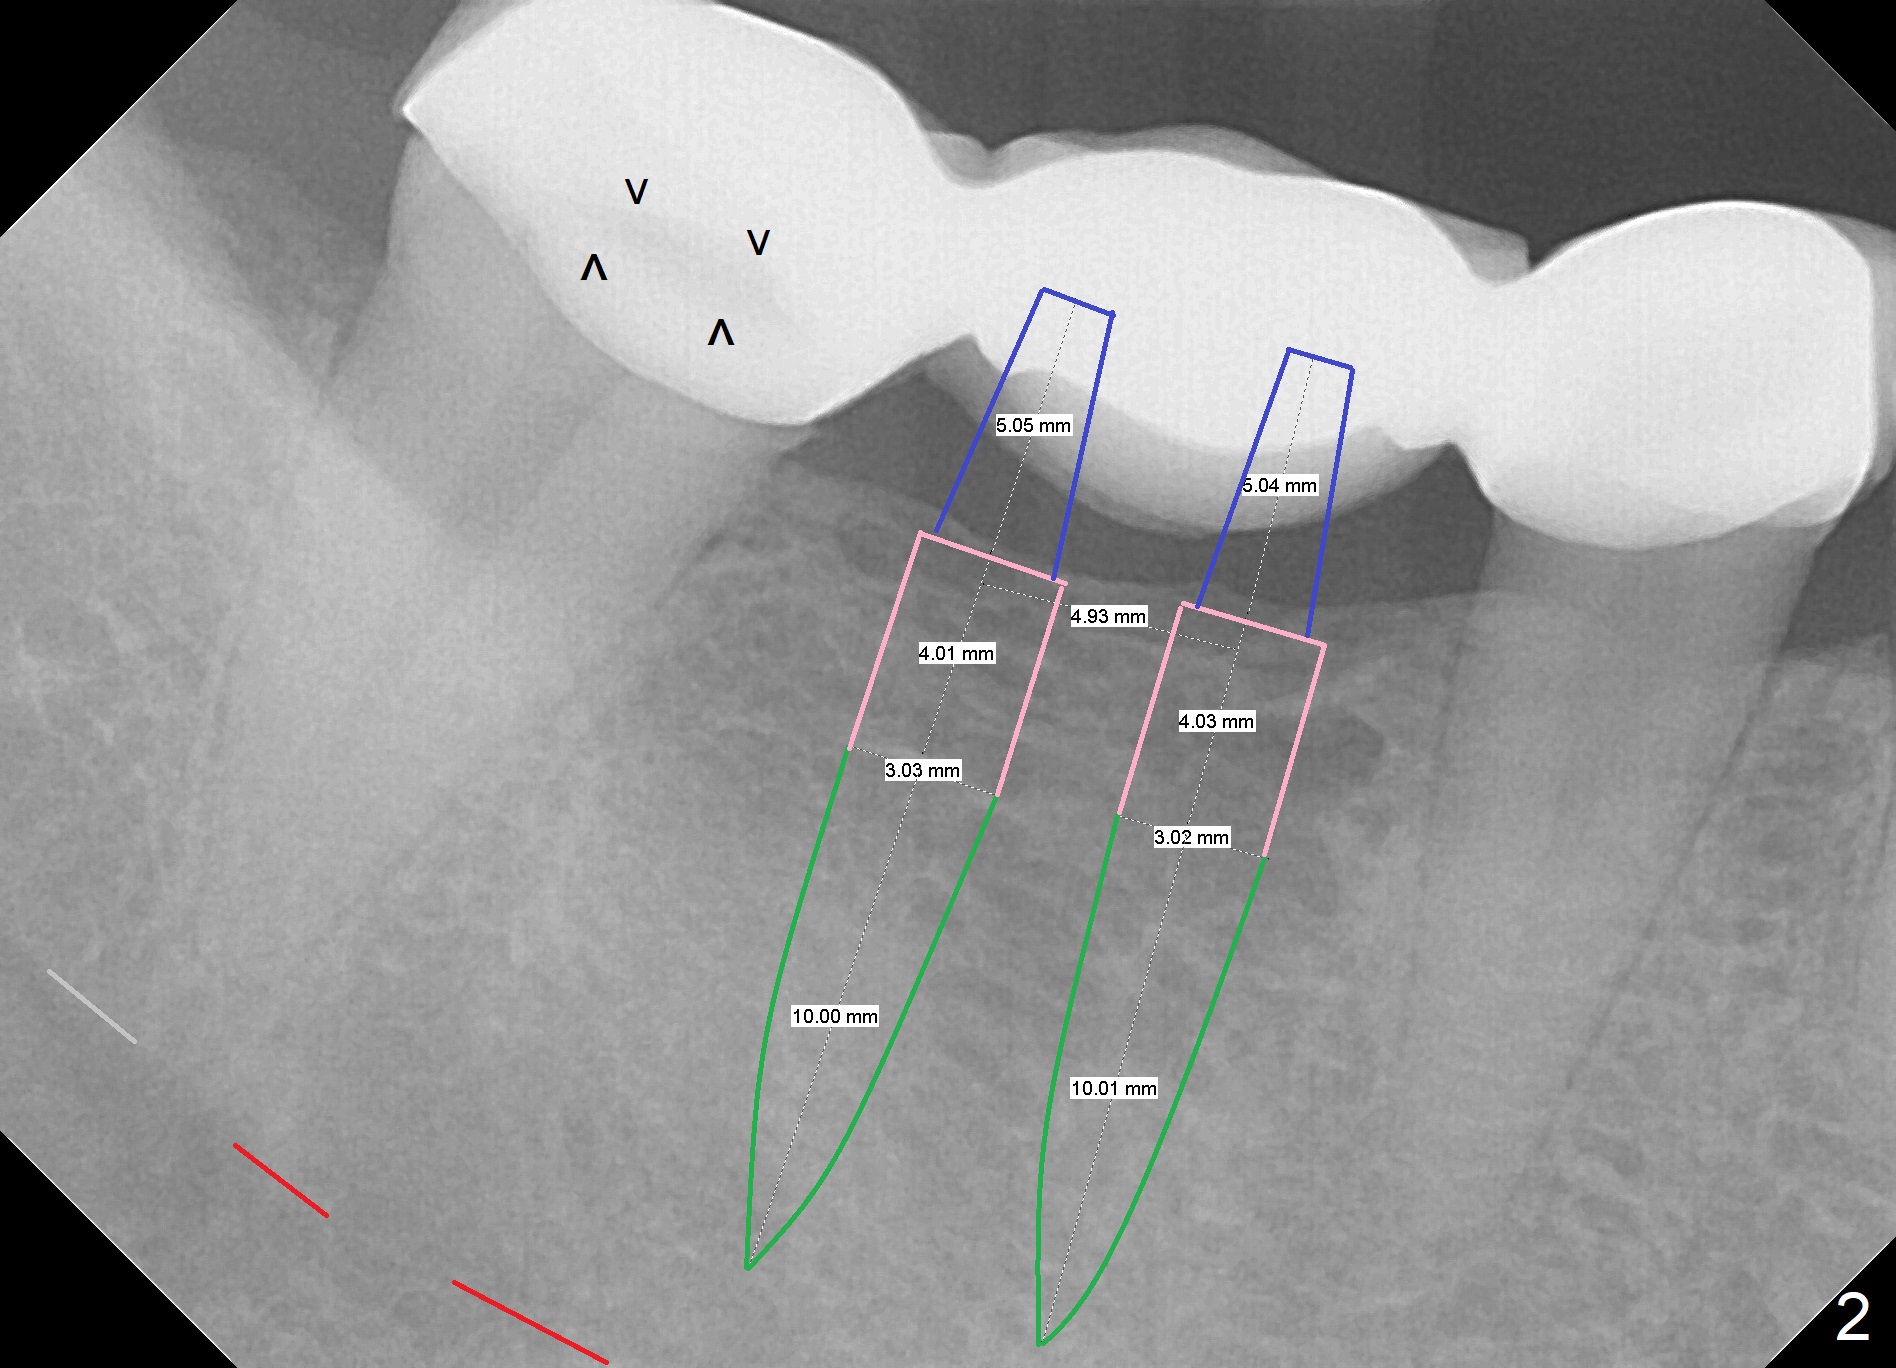

A 38-year-old woman has a loose FPD in the lower right quadrant (Fig.1). The retainer at #31 appears to have open margin (Fig.1 ^) or the abutment has caries (Fig.2 arrowheads). The FPD will be sectioned between #29 and 30. The abutment at #31 needs at least a crown, while an implant will be placed at #30. The bone density at the site is low (Fig.1 pink dashed line). The latter may be due to narrow bone buccolingually. If the ridge atrophy is moderate (e.g. 4 mm (implant positioners)), bone expansion will be executed (Bone Expander Kit or IBS Kit) and a 3.8, 4.1 or 4.5 mm implant will be placed. If the atrophy is severe, the ridge top will be reduced until the ridge is ~ 4 mm, two of 2.5 or 3.0 mm 1-piece implants will be placed (Fig.2). A splinted provisional will be fabricated at #30 and 31.